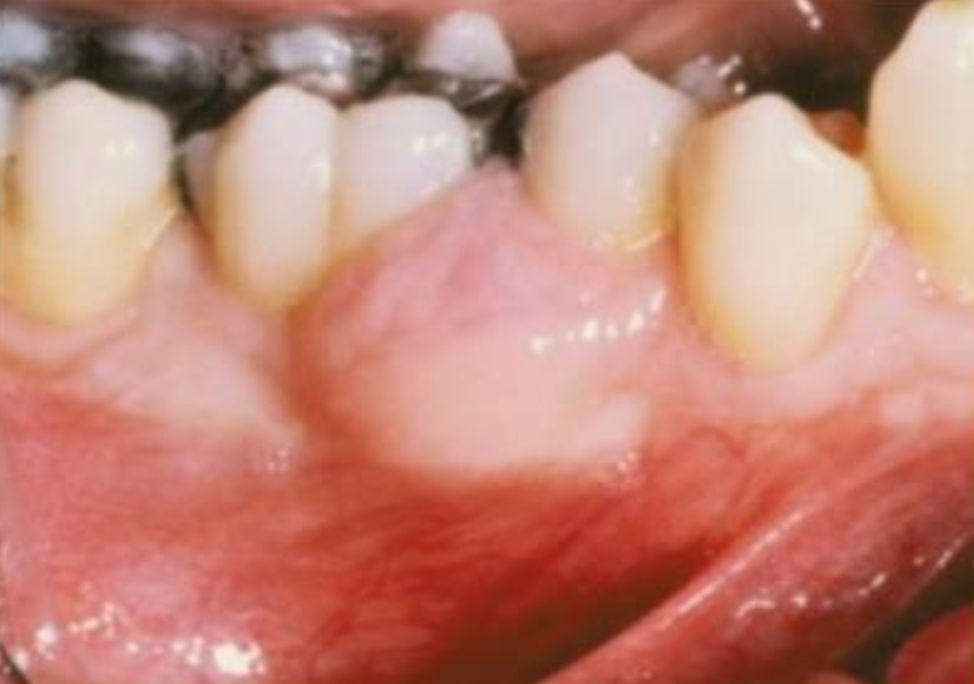

骨外囊腫型(peripheral/ extraosseous) 下顎後、軟組織 52y plexiform 或是 follicular pattern alt text

局部切除, 15-20% 復發